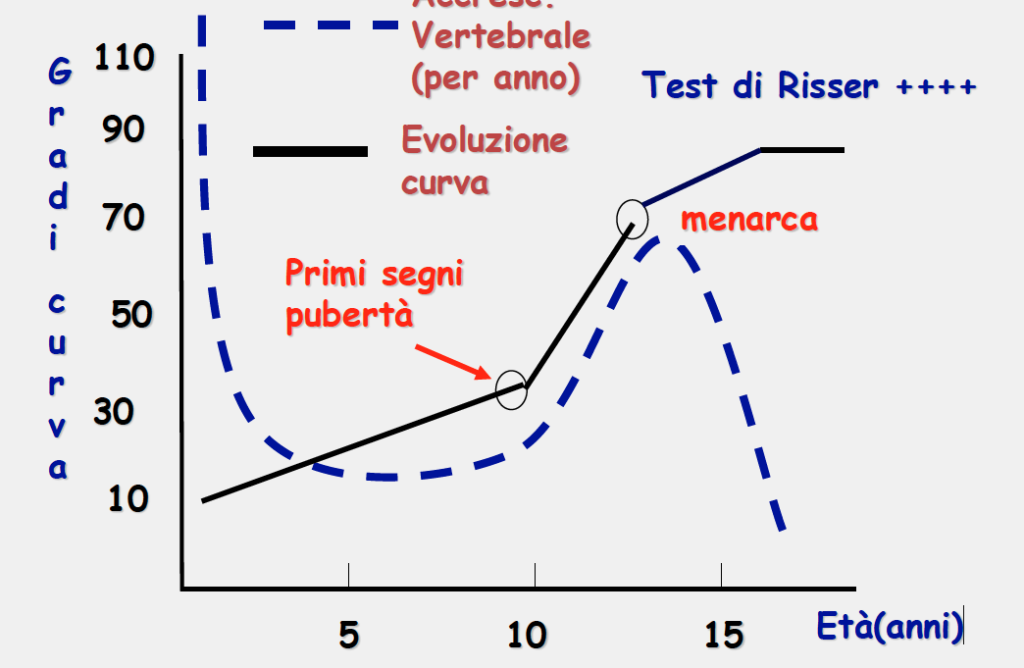

Quella dell’adolescente compare dopo i 10 anni d’età, quindi nella fase dello sviluppo, immediatamente prima dei primi segni di sviluppo sessuale.

Peggiora con la crescita?

Si peggiora in tutta la fase dell’accrescimento e sospende il suo aggravamento alla fine dello sviluppo, attorno ai 16 anni nelle ragazze e ai 17 nei ragazzi, anche se di recente la tendenza di ragazzi e ragazze è a completare prima lo sviluppo dello scheletro. Non tutte peggiorano in modo importante. Sono più a rischio le ragazze dei ragazzi, le ragazze prima del menarca e quando ragazzi/ragazze hanno una maturità dello scheletro ancora immatura, ossia lo scheletro deve ancora svilupparsi .Quelle che peggiorano molto sono circa il 20% del totale In questo grafico introdotto da una geniale dottoressa, si vede il picco di peggioramento dopo i 10 anni.